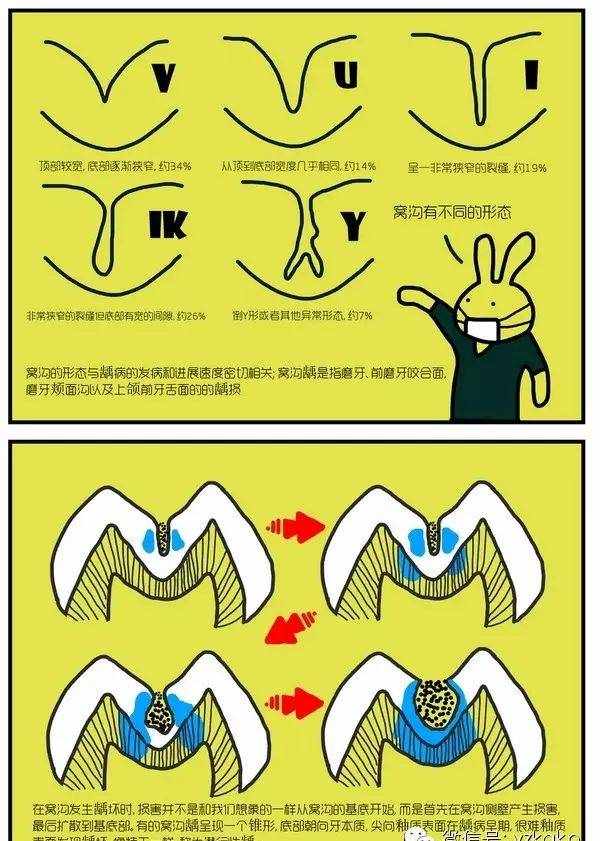

窝沟封闭又称点隙裂沟封闭(pit and fissure sealant),是指不去除咬合面牙体组织,在其上涂布一层粘结性树脂,保护牙釉质不受细菌及代谢产物侵蚀,增强牙齿抗龋能力,从而达到预防龋病发生的一种有效防龋方法。

1.为什么要进行窝沟封闭?

窝沟封闭最重要的作用就是可以避免发生龋齿。饮用水中的氟可以保护牙齿的光滑面,但后牙需要额外的保护。

窝沟封闭剂保护后牙咬合面上的细小窝沟,把食物和细菌隔绝在外。在牙齿龋坏以前给牙齿涂上封闭剂就能有效避免龋坏,从而大大地为患者节约了治疗时间和金钱。

而且,再看看牙齿表面这些深深的“藏身之处”,细菌套路这么深,牙刷也无力把它清扫干净啊。

2.几岁做窝沟封闭?

最佳进行窝沟封闭的年龄是3岁-乳磨牙、6岁-第一恒磨牙、12岁-第二恒磨牙。其它窝沟较深的牙齿也可以做窝沟封闭。